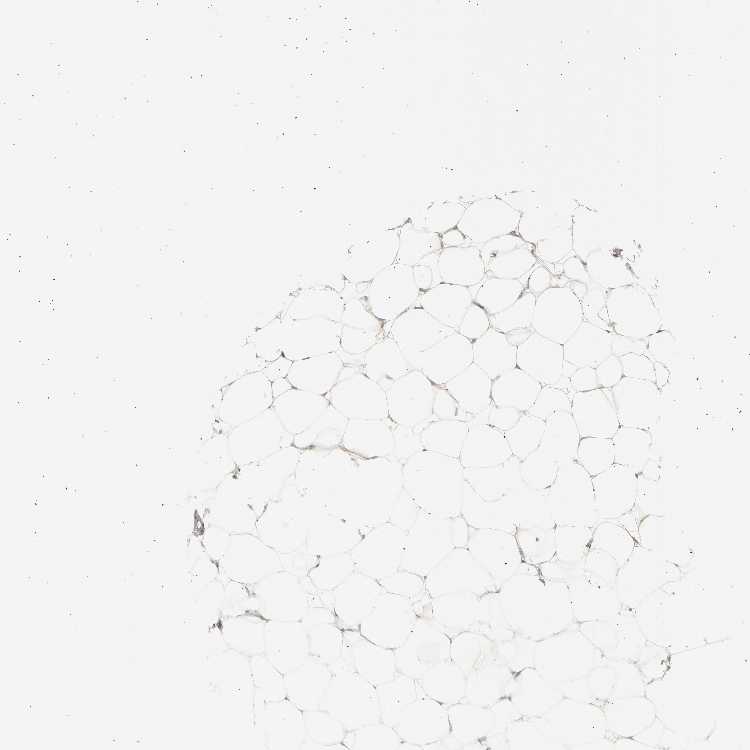

SOFT TISSUE 1 - Antibody stainingi

Antibody staining in the annotated cell types in the current human tissue is reported as not detected, low, medium, or high, based on conventional immunohistochemistry profiling in selected tissues. This score is based on the combination of the staining intensity and fraction of stained cells.

Each image is clickable and will lead to virtual microscopy that enables deeper exploration of all samples and also displays staining intensity scores, fraction scores and subcellular localization as well as patient and tissue information for each sample.

Antibody HPA026488Antibody HPA028425Antibody CAB011203

Chondrocytes Not detected--

Fibroblasts Not detectedNot detectedLow

Peripheral nerve Not detectedNot detectedNot detected

SOFT TISSUE 2 - Antibody stainingi